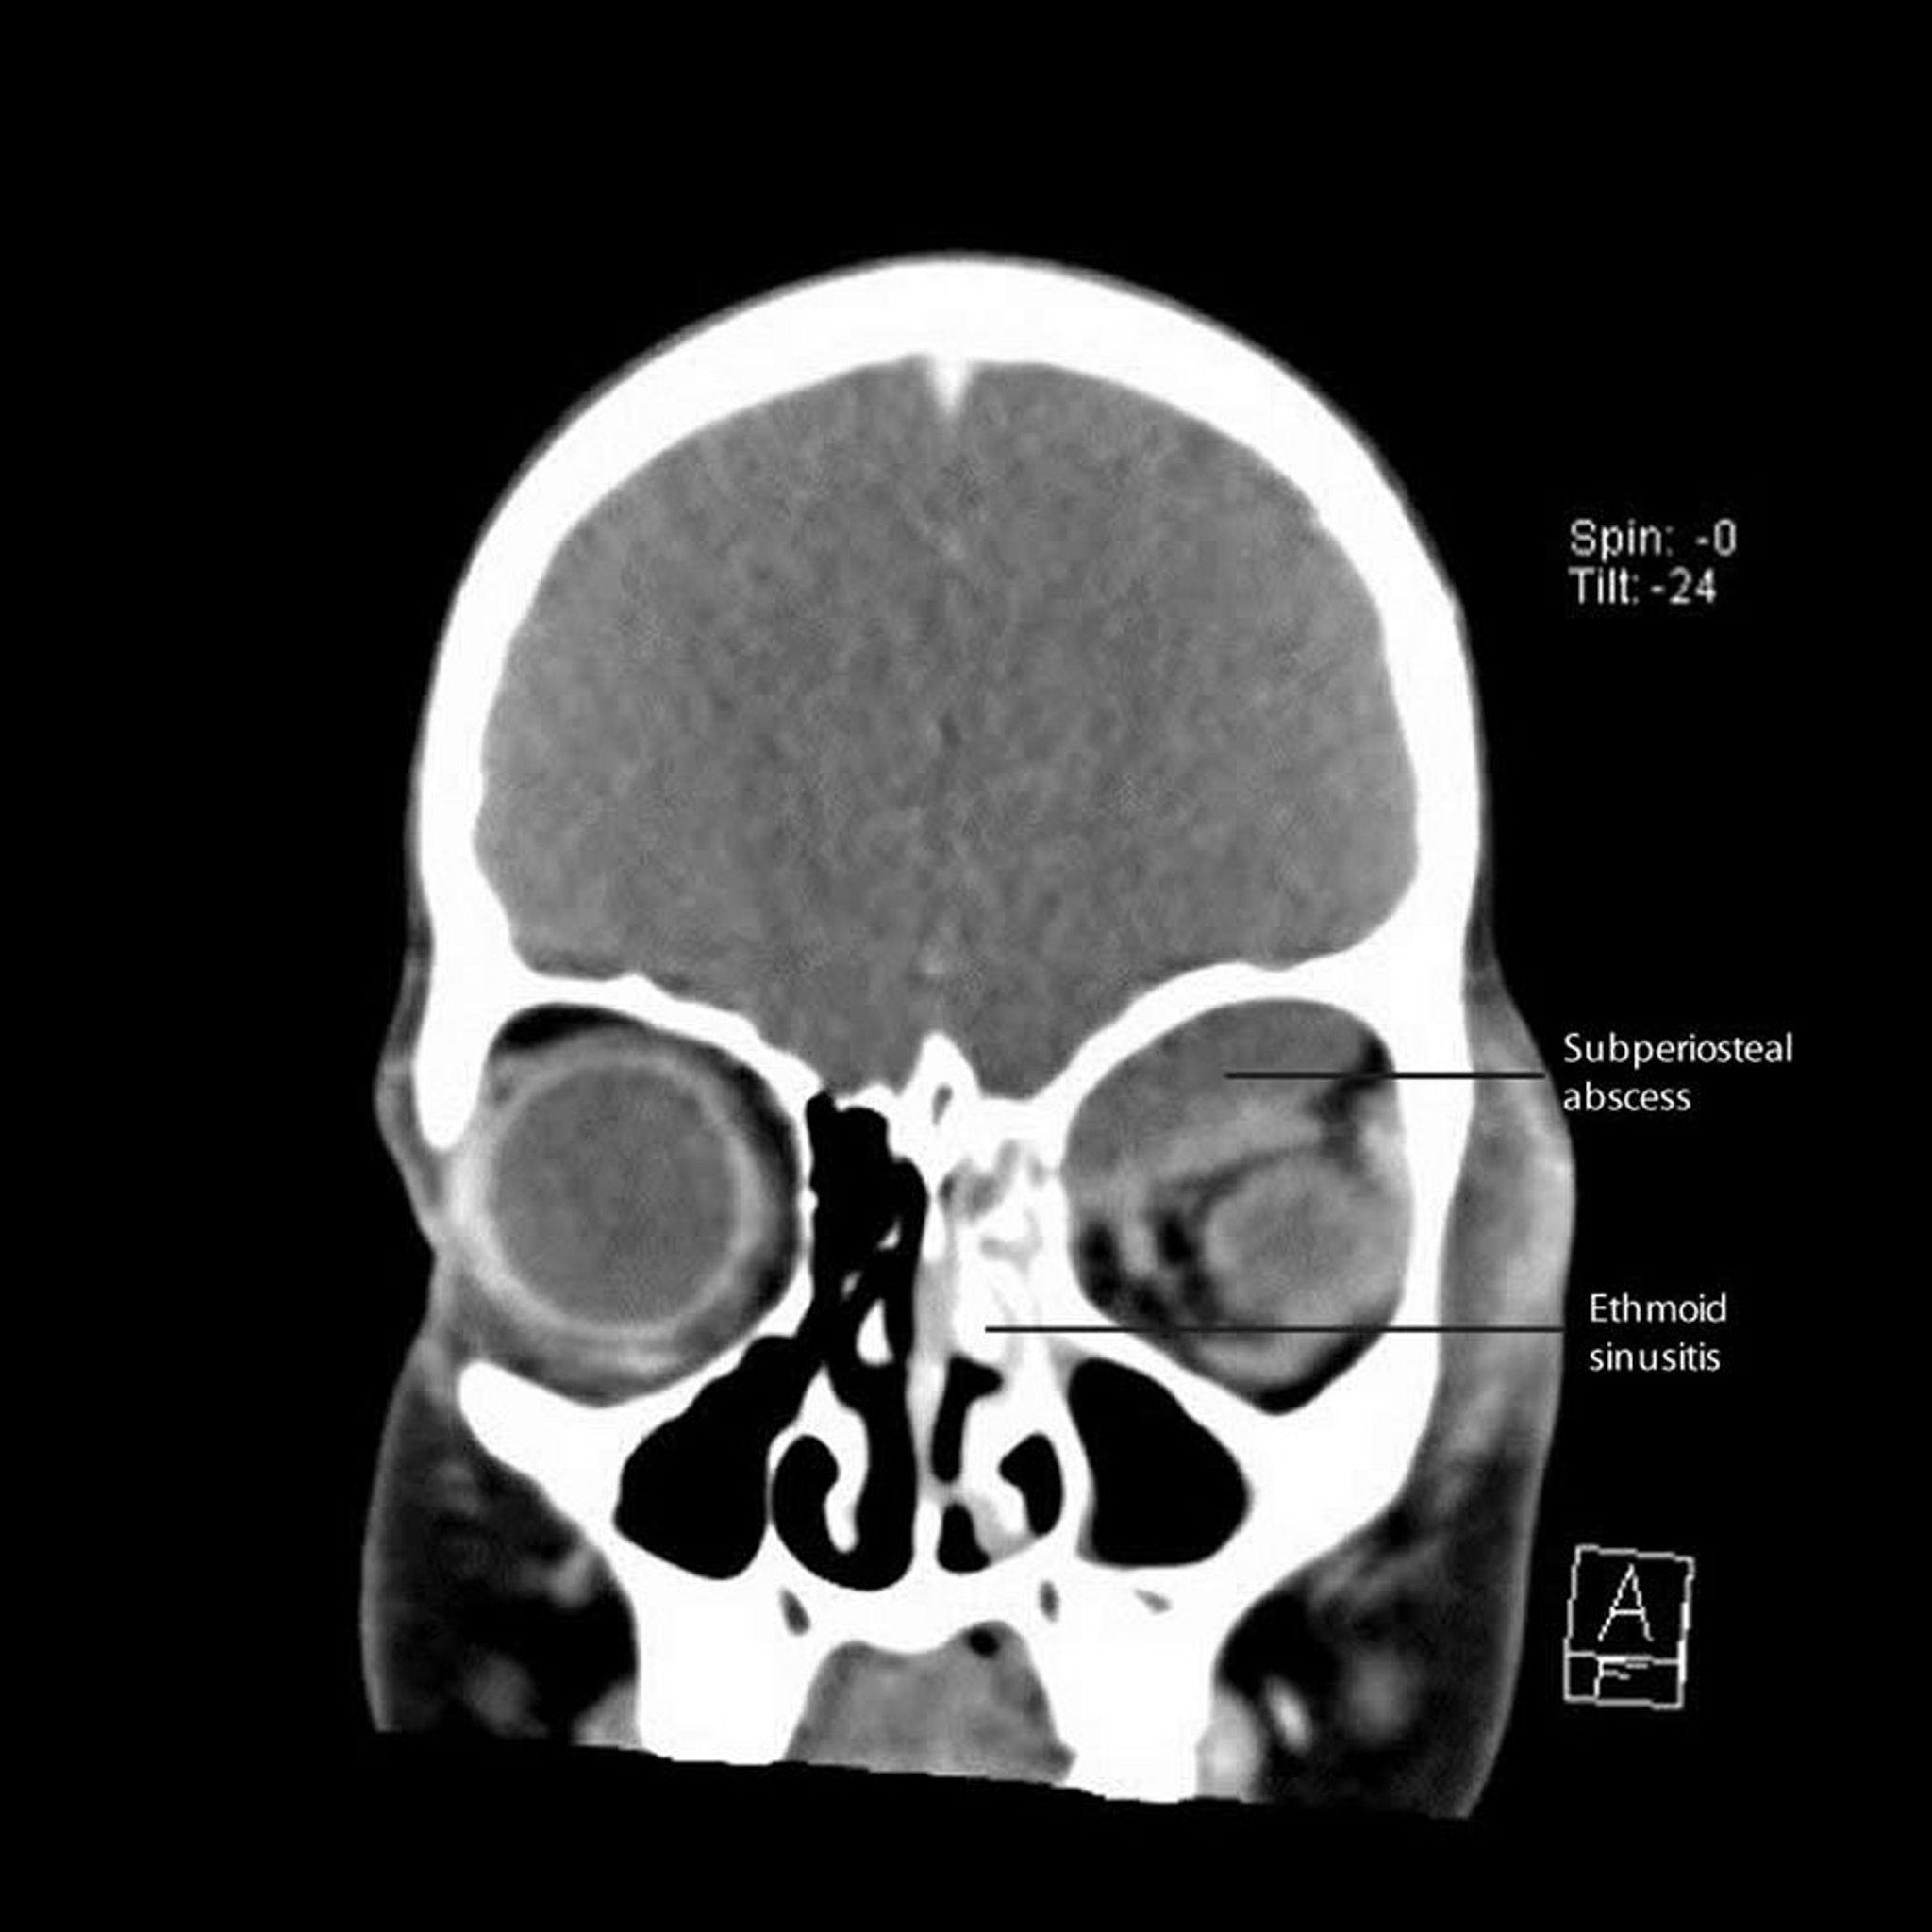

Viêm xoang do Ethmoid với áp xe dưới màng cứng

CT này cho thấy một viêm xoang sàng trái với áp xe dưới sụn lân cận dọc theo thành giữa và mái của hốc mắt.

CT do bác sĩ James Garrity cung cấp.